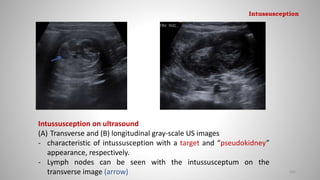

Intussusception on ultrasound

(A) Transverse and (B) longitudinal gray-scale US images

- characteristic of intussusception with a target and “pseudokidney”

appearance, respectively.

- Lymph nodes can be seen with the intussusceptum on the

transverse image (arrow) 105